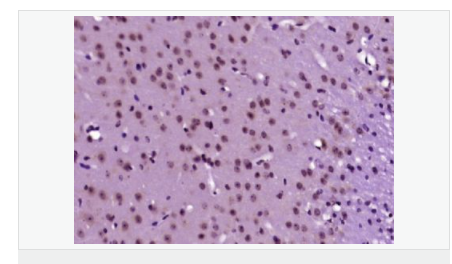

細(xì)胞定位細(xì)胞核 細(xì)胞漿

產(chǎn)品介紹The protein encoded by this gene is a member of the MAP kinase family. MAP kinases act as an integration point for multiple biochemical signals, and are involved in a wide variety of cellular processes such as proliferation, differentiation, transcription regulation and development. This kinase is activated by various cell stimuli, and targets specific transcription factors, and thus mediates immediate-early gene expression in response to cell stimuli. The activation of this kinase by tumor-necrosis factor alpha (TNF-alpha) is found to be required for TNF-alpha induced apoptosis. This kinase is also involved in UV radiation induced apoptosis, which is thought to be related to cytochrom c-mediated cell death pathway. Studies of the mouse counterpart of this gene suggested that this kinase play a key role in T cell proliferation, apoptosis and differentiation. Five alternatively spliced transcript variants encoding distinct isoforms have been reported. [provided by RefSeq, Jun 2013]